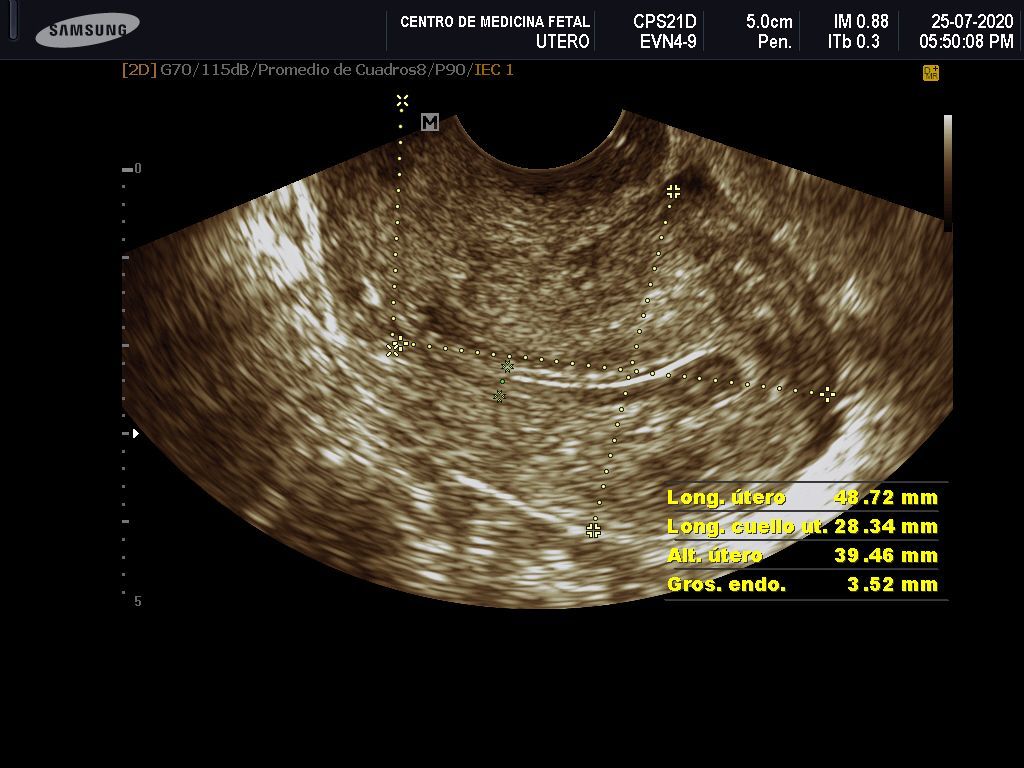

- Detección ecográfica transvaginal o pélvica y tratamiento de: Miomas, quistes de ovario, endometriosis, malformaciones uterinas